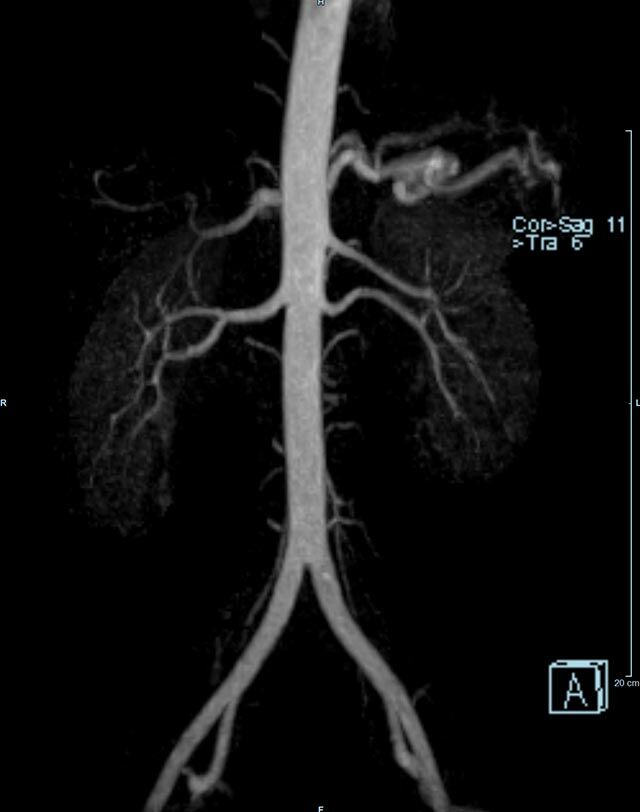

- Bauchgefäße

- Erfassung und Verlaufskontrolle bei arteriellen Aneurysmen (Aussackungen der Arterien), vor allem der Bauchaorta

- Darstellung von Gefäßengen an Nierenarterien, Baucharterien und Becken-/Beinarterien

- MR-Angiographie mit Kontrastmittel

- Erfassung arterieller und venöser Gefäße/Bypässe aller Körperregionen mit 3D-Rekonstruktion

- je nach klinischer Fragestellung zeitaufgelöste MR-Angiographie (4D-MRA) z.B. bei Frage arteriovenöse Fistel/ Shunt oder Darstellung Unterschenkelarterien vor geplanter Bypassoperation.